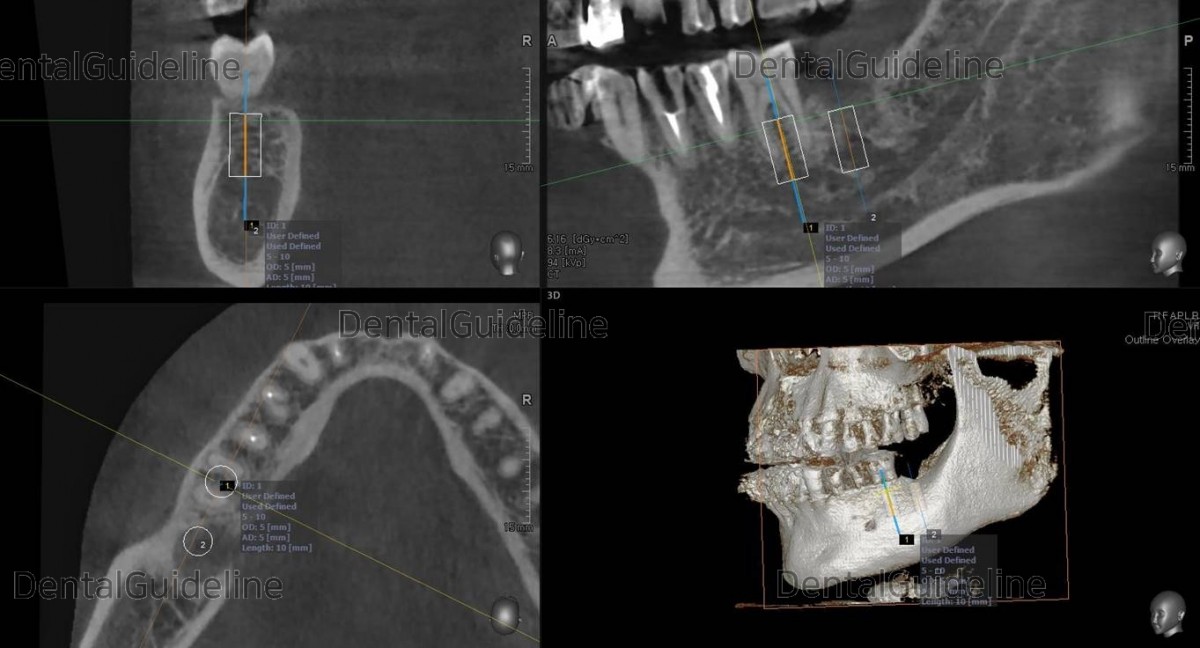

The surgery was simulated simply

![]()

A panoramic radiograph was taken. Arum NB-1 Ø5/10mm

Torque value at the 1st molar and 2nd molar zone. The fixture in the 2nd

molar showed poor initial stability despite less drilling. It was barely 10Ncm.